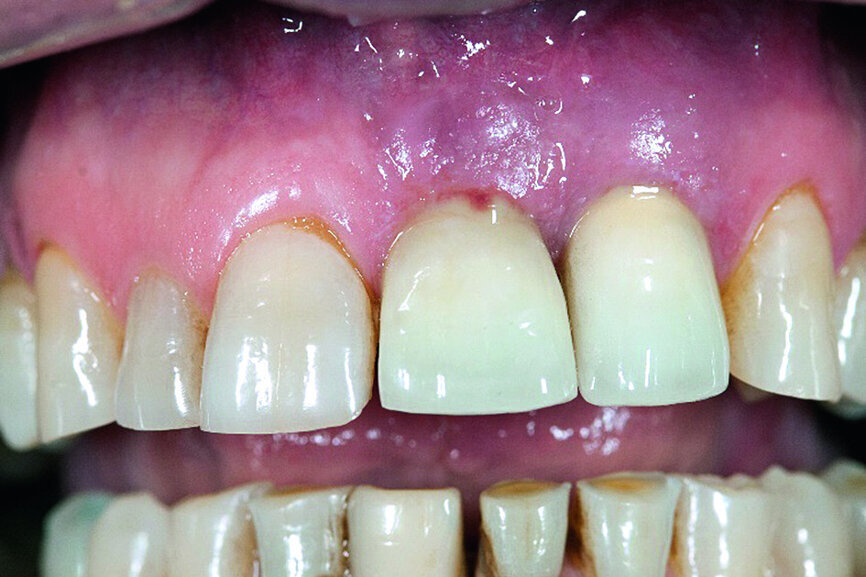

Finally, the surgical area was covered with the bioresorbable membrane, and the flap was re-adapted with interrupted sutures in order to achieve a complete and impermeable wound closure (Fig. 8). The radiograph taken immediately after surgery showed the filled defect (Fig. 9). Good osseous consolidation at the enamel-cement junction of the adjacent teeth could be seen on the follow-up radiograph taken 24 months later (Fig. 10).

The existing scientific findings and the clinical experiences obtained with the presented system, thus allow the conclusion that the protocol proves to be a successful and understandable method for the sanitation of periimplant defects, when lost bone substance is simultaneously regeneratively replaced. The fully synthetically produced, biomimetic beta-tricalcium phosphate granulate has proven to be successful in this treatment. By means of a restitutio ad integrum it is possible to return the weakened implant site not only mechanically, but also biologically, to a functional condition, which is the prerequisite for a successful long-term sanitation.